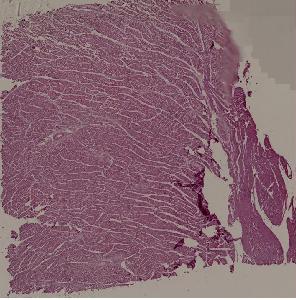

42.风湿性全心炎